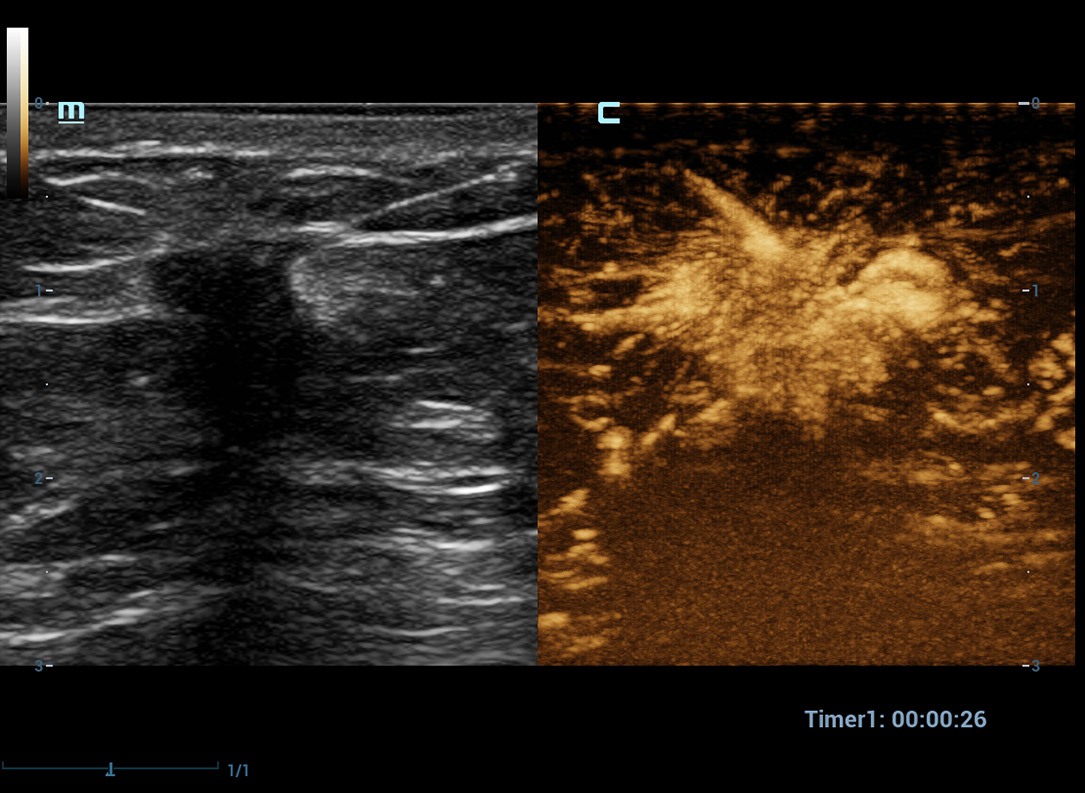

Ultra Micro Angiography (UMA)

UMA migliora la sicurezza diagnostica ampliando la visibilitĂ dei flussi sanguigni fino al livello dei vasi piĂč piccoli, con una sensibilitĂ e una risoluzione superiori.

Massa mammaria pUMA

CEUS UWN+(Ultra-Wideband Non-linear)

CEUS tumore maligno al seno

Utilizzando sia i segnali fondamentali di seconda armonica che quelli non lineari, UWN+ consente un'elevata sensibilitĂ ai segnali delle microbolle e una perfusione di contrasto piĂč lunga con un MI piĂč basso, per contribuire alla valutazione dei tumori.